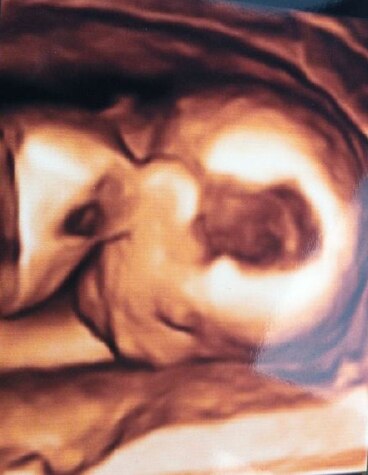

War gestern zur normalen Untersuchung und habe ein 3D Ultraschall bekommen. Wahnsinn! Das nächste mal steh das Screening an, ich bin schon gespannt. Denn letztes mal hieß es: ''so wie es aussieht wird es ein Junge'' und gestern ''so wie es aussieht ein Mädchen''. Also noch mal vier Woche gedulden. Liebe Grüße

Bild zu FA Bericht - Forum für November - Mamis

Wie toll, das ich aber mal ein Geschenk! Ich kann nur leider auf dem Bild nicht viel erkennen, was sieht man darauf?

Das Köpfchen nach unten blickend ;)

..genau, das Köpfchen nach unten :-)